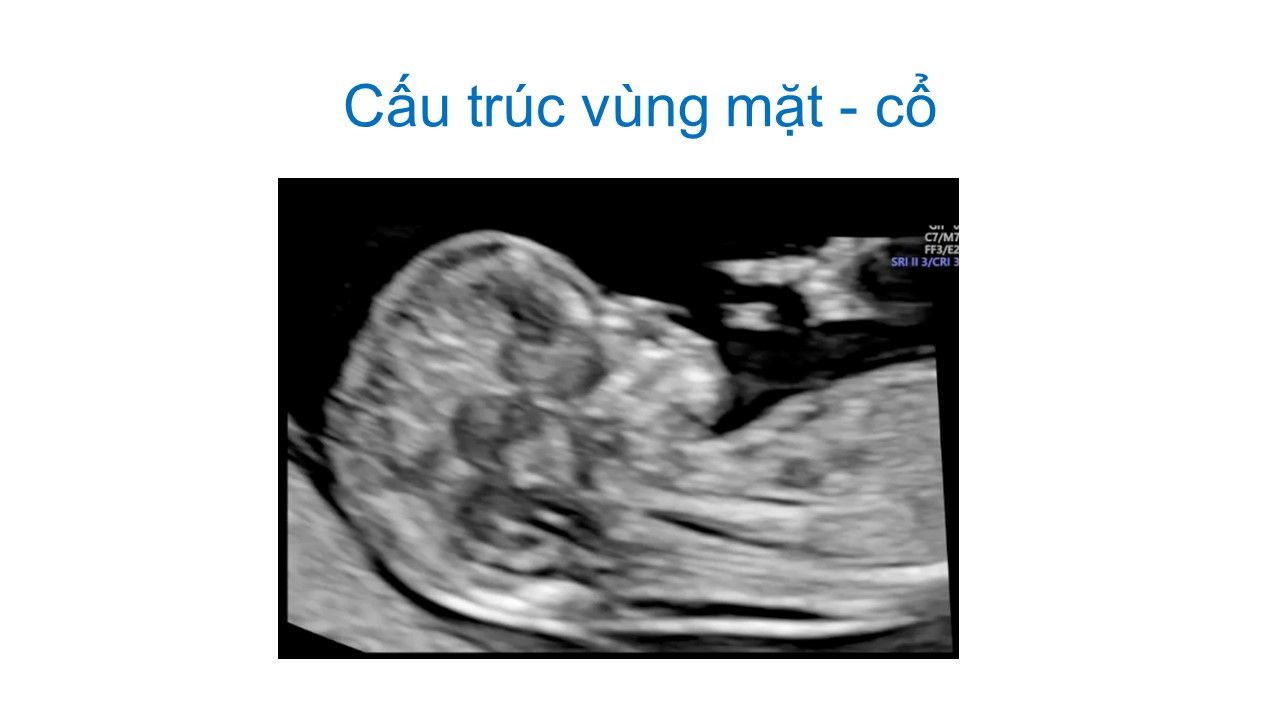

Siêu âm hình thai học quý I

Từ khóa: Siêu âm hình thai học quý I